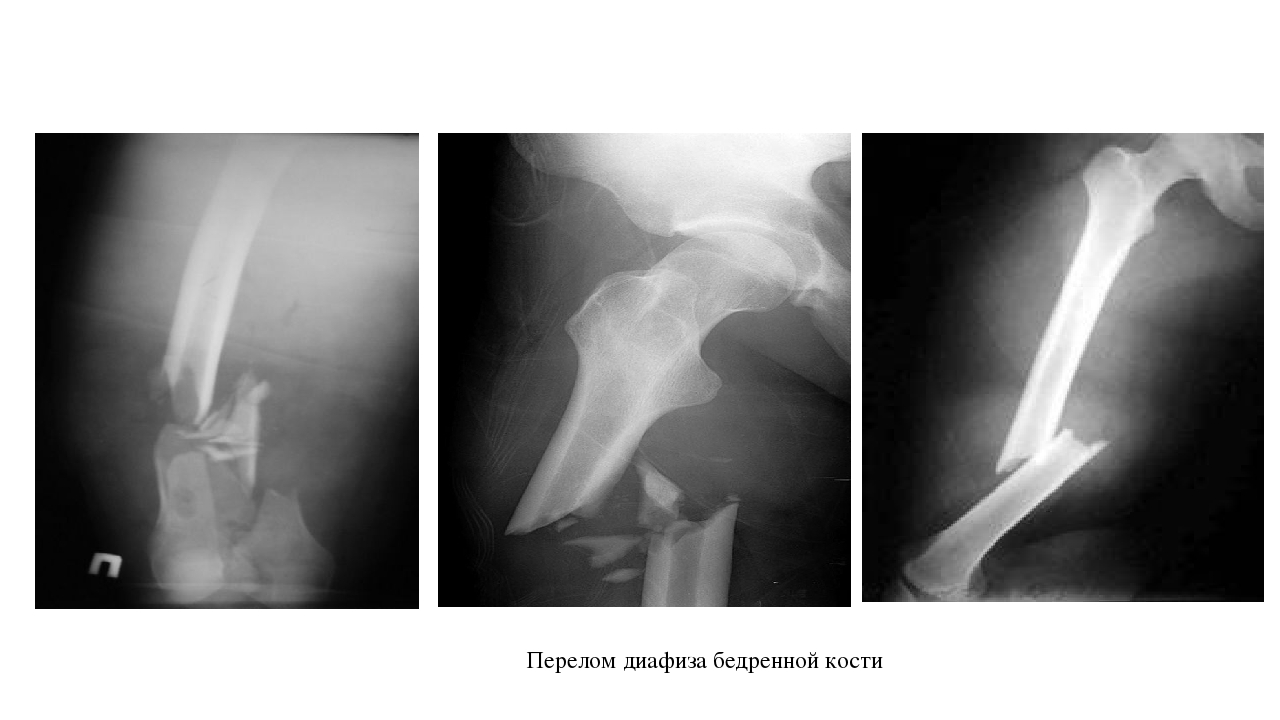

Классификация переломов диафиза бедренной кости: Иллюстрации и информация